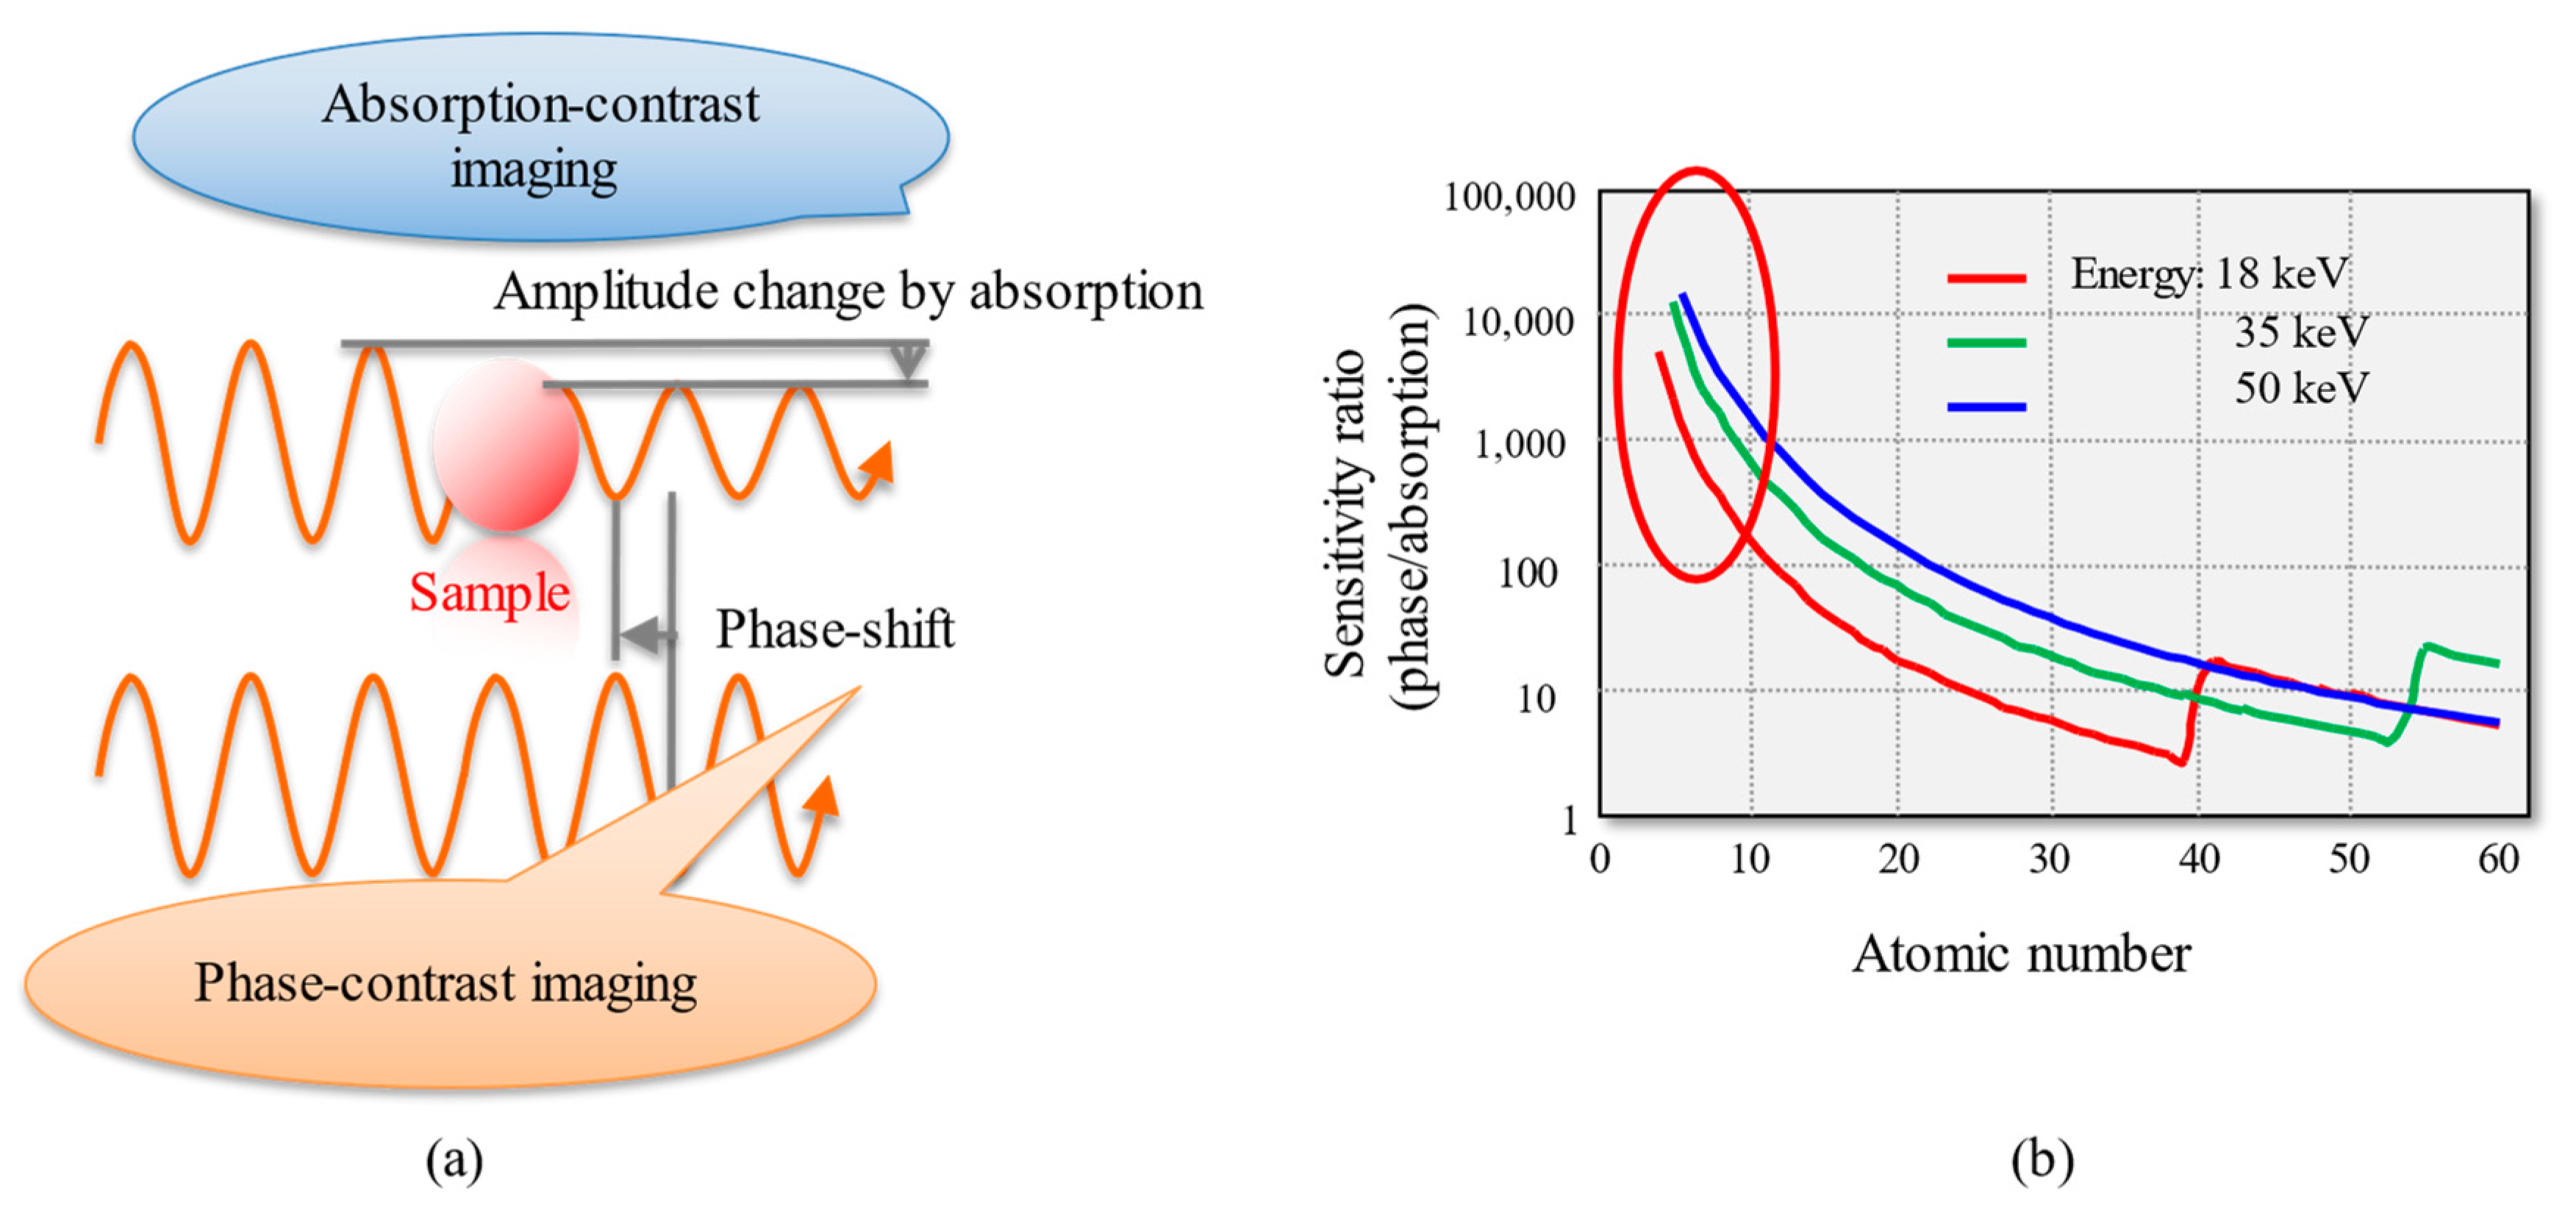

2. Principle of Phase-Contrast X-ray Imaging